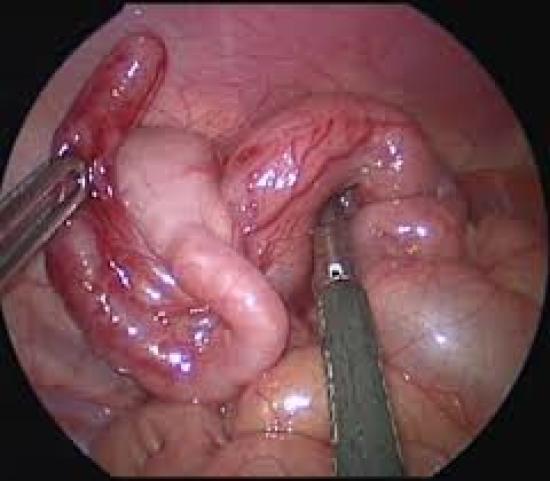

OT Images Of Surgery By Laparoscopy

LAPAROSCOPIC APPENDECECTOMY , surgery can be done through a few small abdominal incisions During a laparoscopic appendectomy, the surgeon inserts special surgical tools and a video camera into your abdomen to remove your appendix. In general, laparoscopic surgery allows you to RECOVER FASTER and heal with LESS PAIN and scarring. It may be better for people who are elderly or obese. But laparoscopic surgery isn't appropriate for everyone. If your appendix has ruptured and infection has spread beyond the appendix or you have an abscess, you may need an open appendectomy, which allows your surgeon to clean the abdominal cavity.